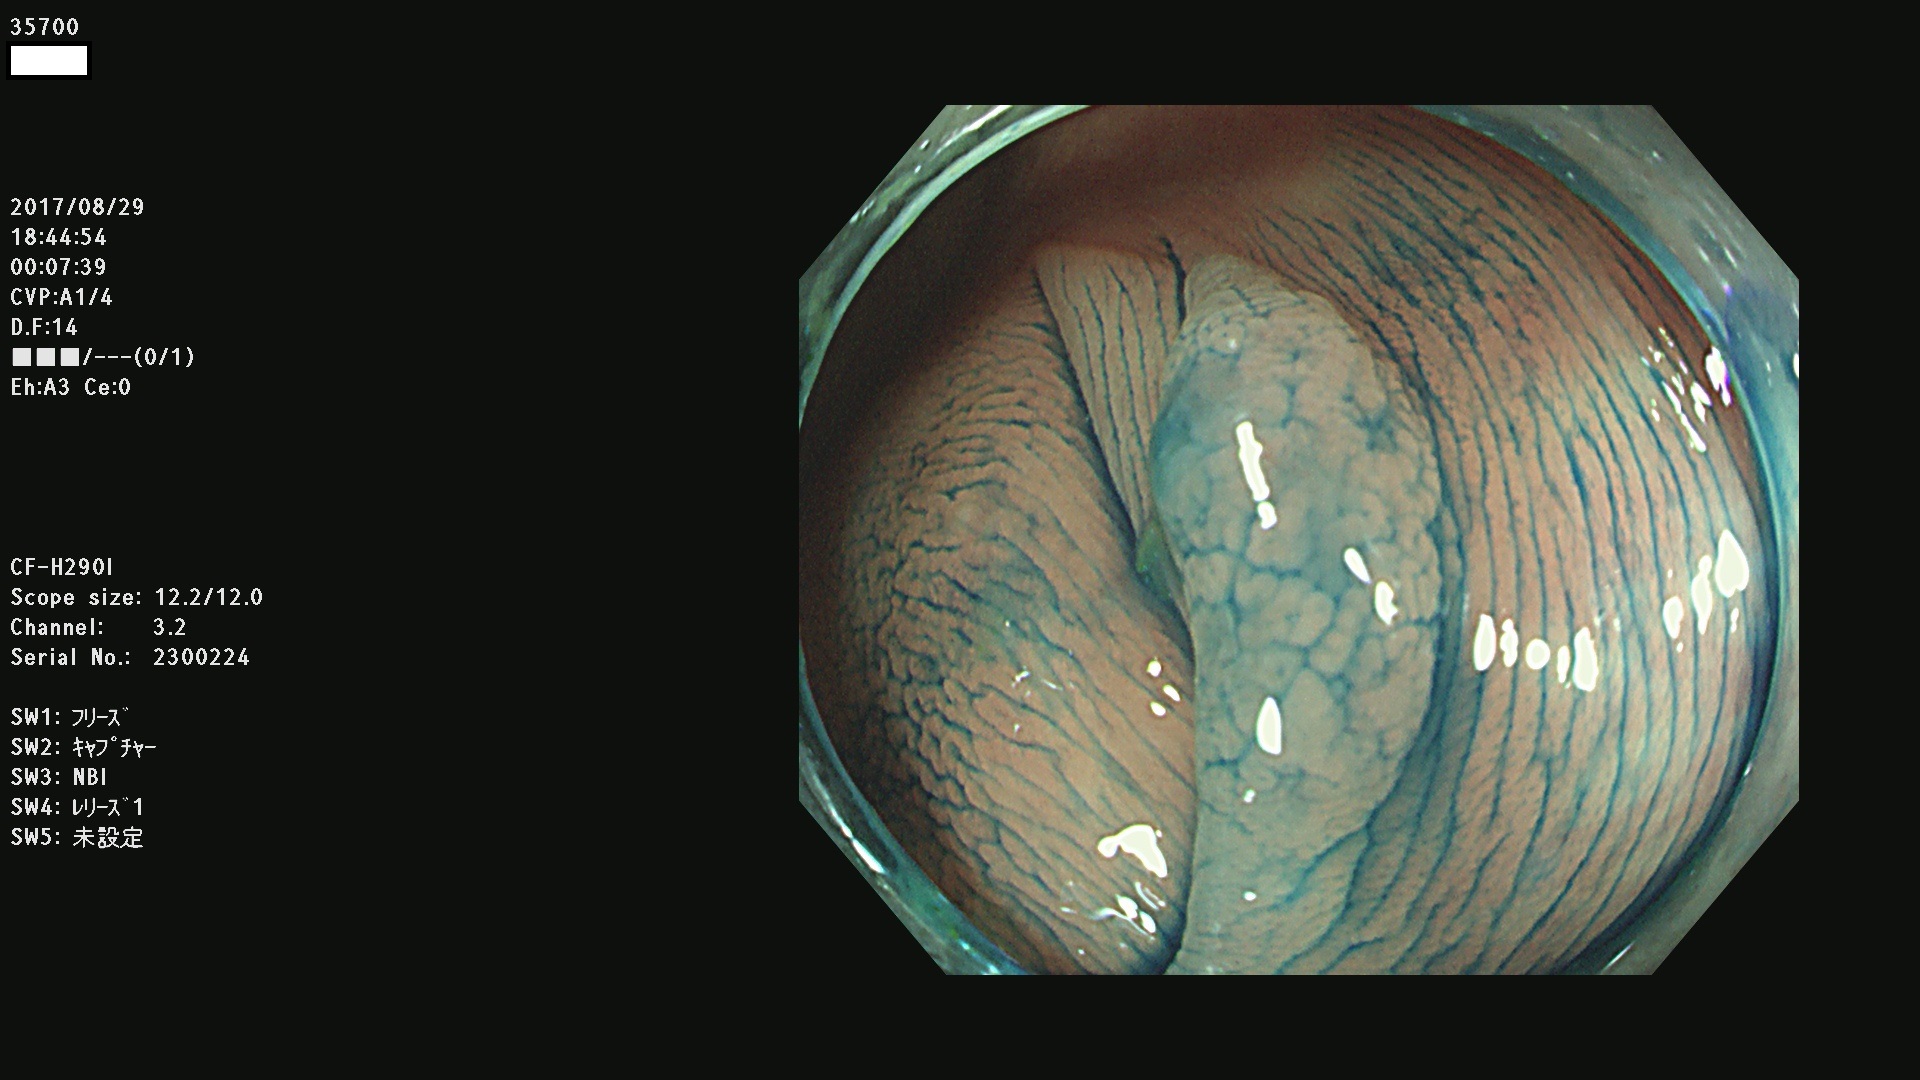

35700 35701 35704 35706 35707 35708 35709 35711(SSA/Pのみ) 35715 35716 35717 35718 35720(SSA/Pのみ) 35722 3576(SSA/Pのみ) 35730 35732 35734(SSA/Pのみ) 35736(SSA/Pのみ) 35741 35742 35743 35744 35746 35748 35749(SSA/Pのみ)35755 35757 35760 35761 35762 35763 35764 35766 35767 35770 35772(SSA/Pのみ) 35773 35781 35783 35785 35786 35787 35788 35791 35795 35796 35797 35798 35799

発見困難で危険性の高い平坦型病変(上記100名より抽出)